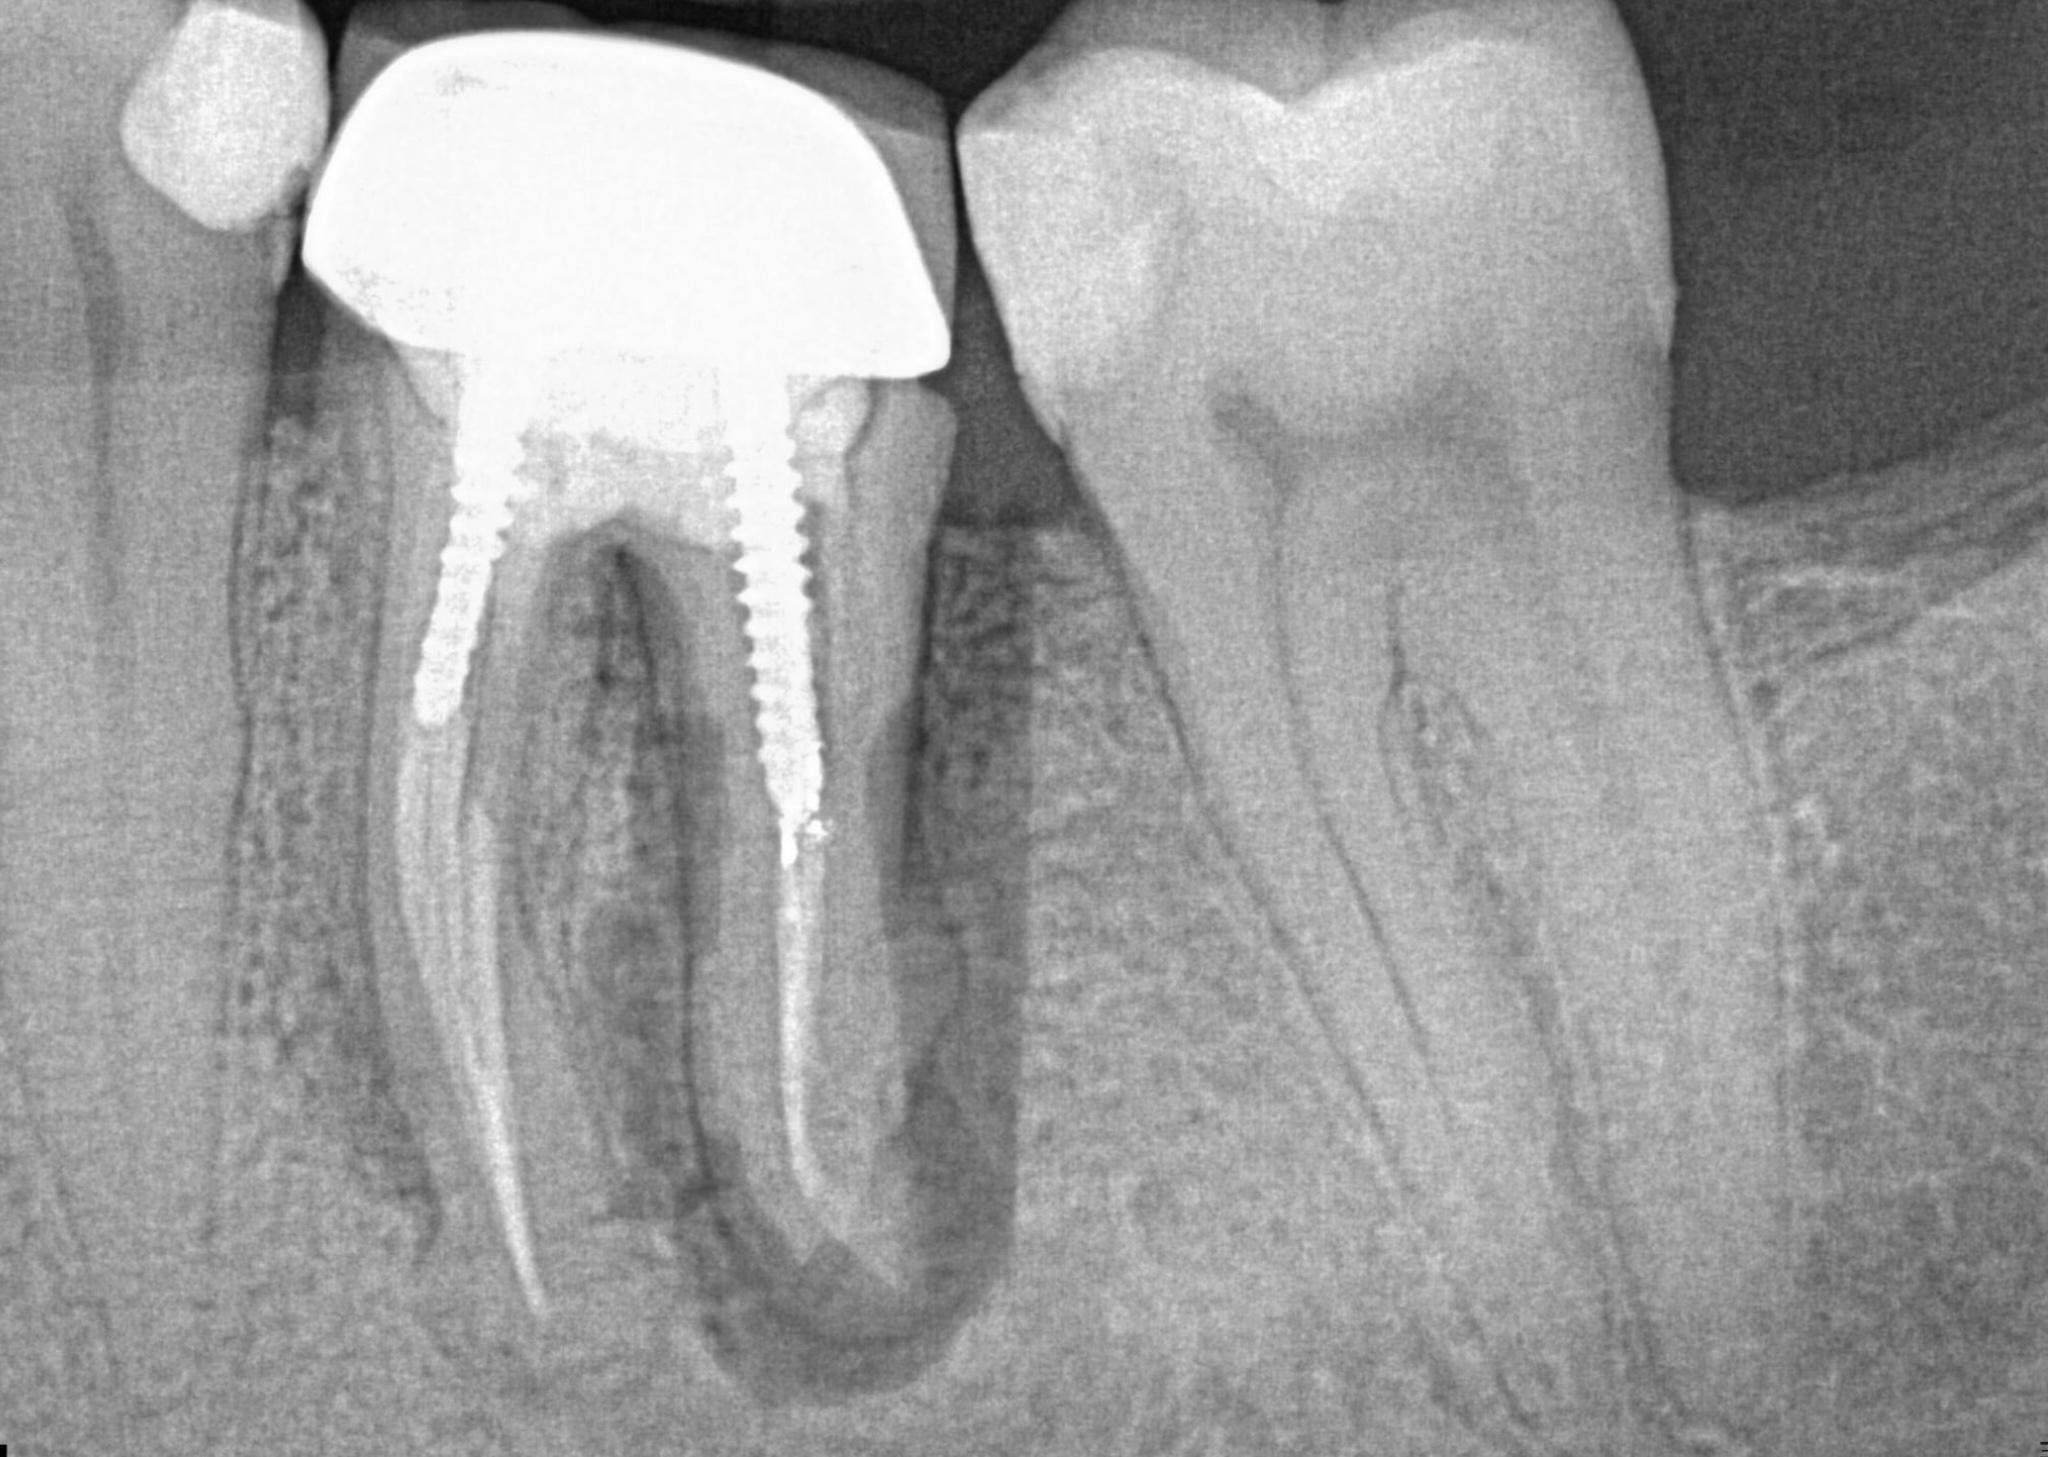

3. What option can describe the post placement in the X ray bellow for the tooth # 3.6?